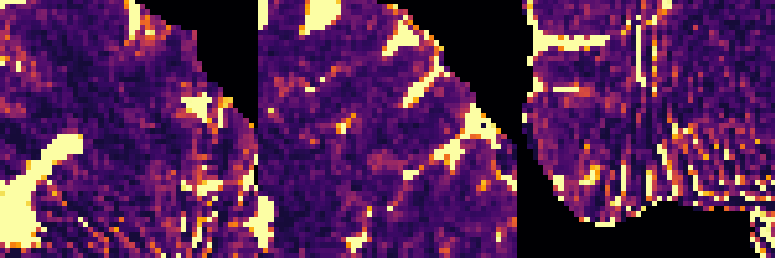

To monitor performance progress, we mapped TSMI to Q-Maps every five epochs. To mitigate the lengthy processing times associated with Dictionary Matching, we implemented a fully connected network to directly map TSMI to Q-Maps [5], significantly reducing processing time. However, for the final assessment, we employed DM on all techniques at the conclusion of the training process (epoch 500). We report in Table 1 the Mean Average Percentage Error (MAPE) of T1/T2 maps, and Peak Signal-to-Noise Ratio (PSNR) and Structural Similarity (SSIM) Index for T1/T2 and normalised PD. To accompany these metrics we also offer in Fig. 2 the reconstructed T1 and T2 maps for the different approaches.

The training and validation loss (Fig. 1) served as valuable guides for architecture and training design. To demonstrate this, we selected a subset of experiments in which we kept certain variables fixed and only modified the one under inspection. From Fig. 1 (a)-(d), MAPEs curves show there is a clear setting with the preferred performance. Specifically, from Fig. 1a, it is evident that using DRUNet yields a clear improvement over the original architecture. This could be attributed to the utilisation of residual units in addition to other architecture differences, such as the choice of upsampling operator (transpose convolution for DRUNet and trilinear for DIP). The choice of input (Fig. 1b) demonstrated a consistent pattern among the tested options, with low rank (conjugate gradient) initialiser marginally outperforming the others. Fig. 1cshows that by epoch 100, stochastic approaches exhibit lower reconstruction errors compared to non-stochastic methods. For example, adaptive LR with stochastic training yields a combined MAPE of 61.40% (17.09% T1 and 44.31% T2) vs. 213.69% (35.50% T1 and 178.19% T2) for the non-stochastic method. This fast convergence is due to adaptive LR and stochastic updates across coils. Despite similar execution times ( 34 min for stochastic with adaptive LR vs. 32 min for non-stochastic with fixed LR), the rapid error reduction makes StoDIP more attractive for training.. To assess the early stopping of DIP models, a key element, we present Fig. 1d. The original work by Ulyanov et al. [21] used 2k iterations, while Hamilton et al. [12] used 30k. In contrast, our settings show StoDIP achieving competitive performance in under 500 epochs (4k iterations) on the entire volume. However, StoDIP can overfit to k-space measurements, affecting reconstruction accuracy, and thus the iteration at which it stops could have a greater impact. We show that adding a spatial penalty term addresses overfitting and instabilities. This is supported by the maps in Fig.2, supplementary material Figures 1-3, and metrics in Table 1. StoDIP reconstructions lack aliasing artifacts, and the TV regularizer (StoDIP + TV) further improves Q-Map reconstruction by reducing checkerboard artifacts observed in StoDIP outputs alone.